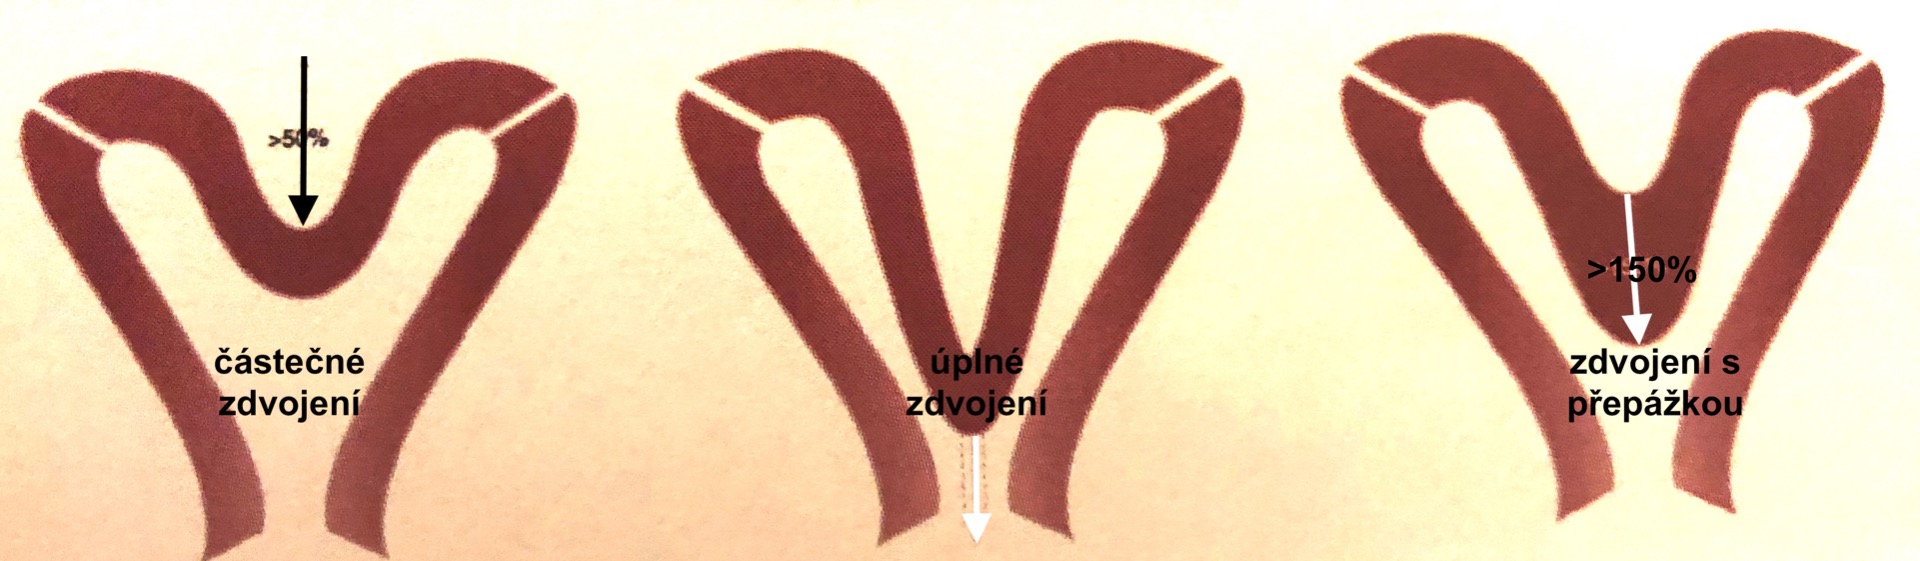

- Děloha s částečnou nebo úplnou přepážkou v děložní dutině-uterus subseptus, septus

Patří sem všechny případy normálního spojení dolní části obou Müllerovy vývodů. Vznikne kanál, ale nevymizí střední část, proto je dutina děložní částečně nebo úplně rozdělená střední přepážkou-septem, která je větší než 50% tloušťky děložní stěny. Přepážka může zasahovat až do děložního čípku a do pochvy. Přesná diagnóza je možná pouze 3D ultrazvukovým vyšetřením, kterým odlišíme dělohu s přepážkou (uterus septus, subseptus) od dělohy se zdvojeným děložním tělem (uterus bicornis). Odlišení je velmi důležité, protože přepážku můžeme odstranit hysteroskopicky a tím snížíme riziko komplikací, které může děloha s přepážkou v těhotenství působit.

U dělohy s přepážkou je vyšší riziko spontánního potratu a předčasného porodu.

- Děloha se zdvojeným děložním tělem-uterus bicorporeus (dřívější název uterus bicornis-dvojrohá)

Vzniká jako chyba splynutí Müllerových vývodů. Děloha má abnormální zevní tvar. Vklesnutí vrcholu stěny děložní je větší než 50% její tloušťky. Vklesnutí může částečně nebo úplně rozdělit děložní dutinu a může se rozšířit až na děložní čípek a pochvu. Na třetím obrázku vidíte, že se také nemusí vstřebat středová přepážka.